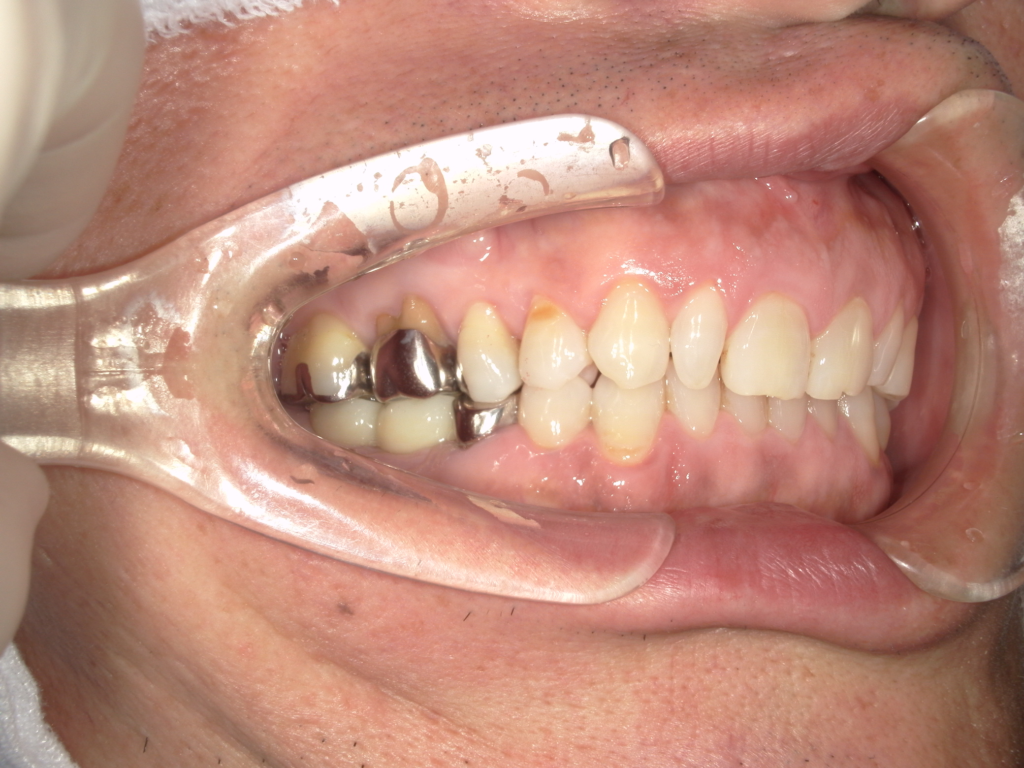

Y様インプラント実例 #44

左の上下の奥歯をインプラントで治療しています。

左下の奥歯は歯を抜くのと同時にインプラントの埋め込みを行っています。

被せものは上下、セラミックスで作っています。

治療前

治療後